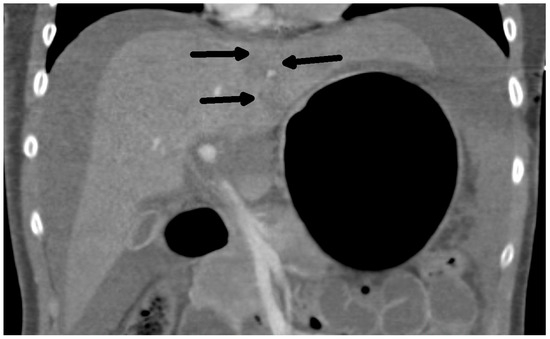

Rare Complication of Cardiopulmonary Resuscitation—Liver Injury

by David Hoskovec, Pavol Klobušický, Adam Pudlač, Matyáš Lochman, Zdeněk Krška and Petr Dytrych

Medicina 2024, 60(9), 1470; https://doi.org/10.3390/medicina60091470 - 9 Sep 2024

Background and Objectives: Liver injury is a rare complication of cardiopulmonary resuscitation. Correct and early diagnosis and treatment are essential. The clinical signs of injury may be masked by the cardiac arrest. We present a single-centre retrospective observational study of traumatic liver [...] Read more.

Background and Objectives: Liver injury is a rare complication of cardiopulmonary resuscitation. Correct and early diagnosis and treatment are essential. The clinical signs of injury may be masked by the cardiac arrest. We present a single-centre retrospective observational study of traumatic liver injury after cardiopulmonary resuscitation. Materials and Methods: A retrospective analysis of the patients treated for liver injury after cardiopulmonary resuscitation was conducted. Demographic data, the cause of resuscitation, the duration of restoration of spontaneous circulation (ROSC), and the surgical approach were analysed. Results: We have treated nine patients with severe liver injury after cardiopulmonary resuscitation. The diagnosis was made on the basis of cardiopulmonary instability, a fall in the erythrocyte count in eight cases, and was confirmed by CT or ultrasound examination. The last one was diagnosed accidentally on MR. Surgery, in cases of unstable patients, was followed immediately after a diagnosis. We combined liver sutures and intra-abdominal packing with a planned second-look surgery. Five of the nine patients survived. Conclusions: Liver injury after cardiopulmonary resuscitation is rare and is associated with high mortality. The recurrence of cardiopulmonary instability and/or a low or falling red blood cell count are the main signs of this injury. Bedside ultrasound and CT scans are the most important methods to confirm the diagnosis. The rule of surgical repair is the same as in all liver injuries, regardless of aetiology. The key factors for survival include early diagnosis, together with the length of restoration of spontaneous circulation (ROSC). Full article

Show Figures

Figure 1